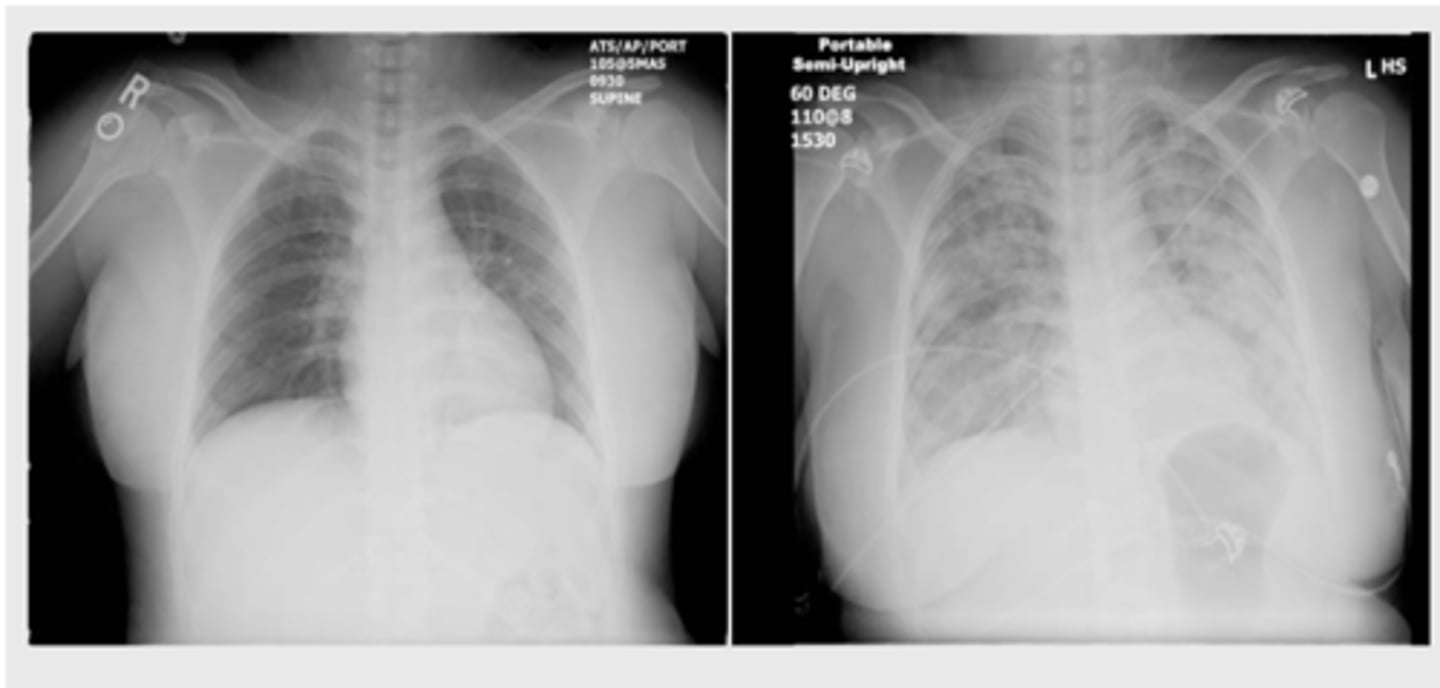

tachycardia, cough, dyspnea, hypertension; cardiomegaly and pulmonary edema are seen on CXR

What are signs and sx of Transfusion-Associated Circulatory Overload (TACO)?

measuring a BNP/NT-proBNP may assist; echocardiogram (know your patient’s EF)

How is Transfusion-Associated Circulatory Overload (TACO) dx?

diuresis and supplemental oxygen; ventilation support may be required

Non-cardiogenic pulmonary edema causing acute hypoxemia within 6 hours of the transfusion with clear temporal relationship to the transfusion

What is Transfusion-Related Acute Lung Injury (TRALI)?

Antineutrophil cytoplasmic antibodies or anti-HLA antibodies activate the recipient's immune system

What causes edema in Transfusion-Related Acute Lung Injury (TRALI)?

TRALI

Donor products that contain large amounts of plasma from multiparous women are associated with: